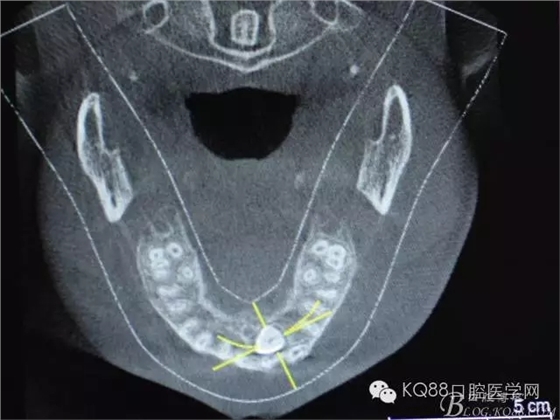

圖1.術(shù)前的cbct影像檢查:23位于腭側(cè)、牙齒位置比較高。